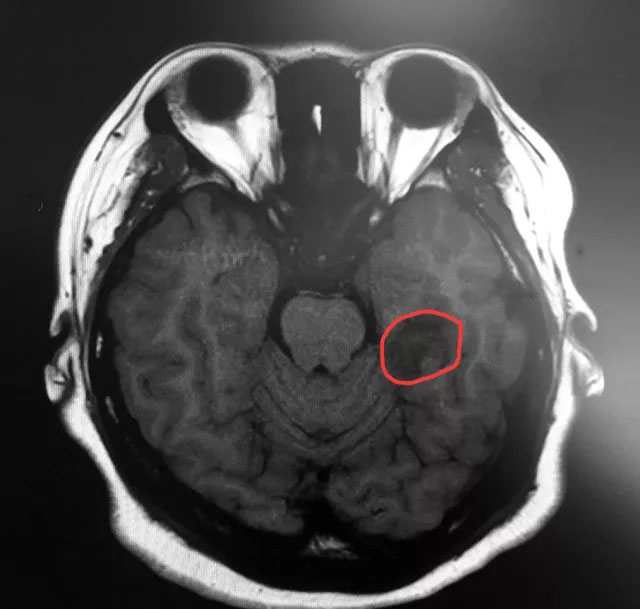

▲標記處為患者腫瘤部位

近日,上海藍十字腦科醫(yī)院神經(jīng)外科6B病區(qū)收治了一名癲癇患者。今年三月初,25歲的袁女士(化名)突然出現(xiàn)“陣發(fā)性無法對答、閉目、呆立不動、吞咽唾液、意識喪失”等癥狀,一個月偶爾發(fā)作一次,當時患者和家人也沒在意。但近三個月患者發(fā)作頻繁,嚴重時一天多達三四次,家人明顯感覺不對勁,之后就診于當?shù)蒯t(yī)院,并進行了頭部MRI檢查,影像學(xué)顯示:患者左側(cè)顳葉(海馬區(qū))囊實性占位。

據(jù)吳治群博士介紹,袁女士的癲癇比較特殊,她不單單是左側(cè)顳葉(海馬區(qū))囊實性占位引起的癲癇,同時還合并額葉癲癇,這種情況在臨床中也是不多見的。對于繼發(fā)性癲癇的治療,吳治群博士指出,首先要去除引起患者癲癇的因素,這樣對因治療效果才會更好;而袁女士左側(cè)顳葉(海馬區(qū))明顯占位,屬于繼發(fā)性癲癇,病因明確,通常首選手術(shù)治療癲癇。